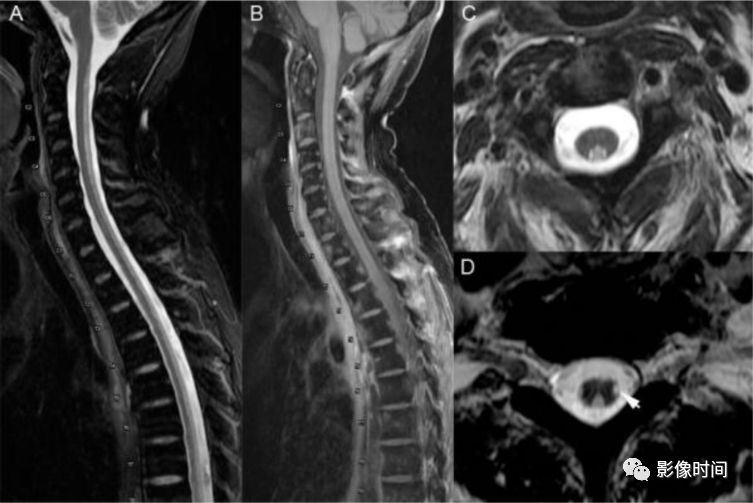

神经脊髓炎谱系疾病(neuromyelitis optica spectrum disorder,NMOSD):是一种由水通道蛋白-4(AQP-4)自身抗体介导的炎性脱髓鞘疾病,青年或中年女性较多见,临床常为双侧视神经炎和脊髓炎导致失明和截瘫,也可累及大脑。

MRI:

脊髓:病灶 T2WI 呈高信号,T1WI 呈稍低信号,急性期出现斑片状或云雾状强化,轴位常位于脊髓中央,长度>3 个椎体长度。亮点征:轴位 T2WI 很高信号的多发斑点,信号高于脑脊液,特异性=97%。

病灶分布于脊髓中央,长度大于3个椎体,亮点征

视神经:双侧视神经广泛受累,病灶长度通常>1/2 视神经长度,优先损害后视通路,包括视神经颅内段、视交叉和视束,急性期 T2WI 视神经肿胀伴明显高信号,T1WI 视神经明显强化,后视通路为主。

后视路受累为主,明显强化

大脑:AQP4 通道是中枢神经系统最丰富的水通道,在室管膜周围、下丘脑和软脑膜下区以及脑干、极后区均有高表达。因此,高表达 AQP4 的特定区域成为 NMO 自身免疫靶点

多发性硬化(Multiple sclerosis,MS)亦是一种严重的中枢神经系统自身免疫脱髓鞘病变,免疫球蛋白分泌 B 细胞和浆细胞的克隆性扩增,可使 CSF 中出现寡克隆带特征。

脊髓:颈髓较常受累,病灶 T2WI 呈高信号,T1WI 呈稍低信号,轴位常分布于前索、侧索或者后索,长轴 ≤ 2 个连续阶段椎体,急性期呈斑片状、结节状或环形强化。

病灶位于侧索、长度小于3个椎体节段